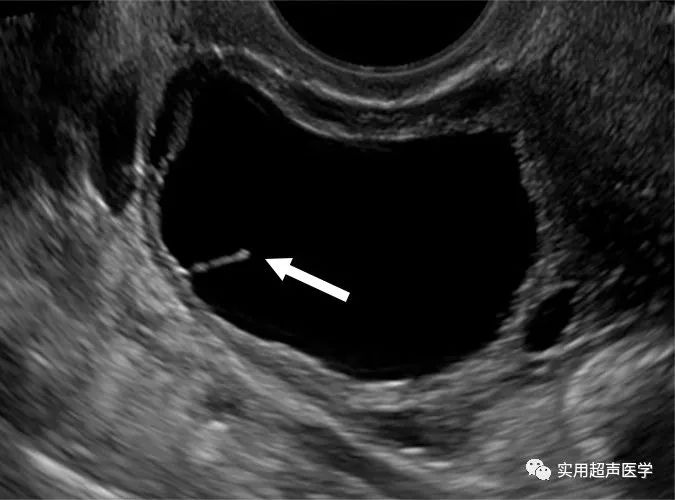

28岁女性,子宫异常出血和良性卵巢囊肿。超声图像显示偶然检测到的左卵巢单房囊肿,伴有不完全分隔(箭头)。对于适当的 O-RADS 分类,该病变被认为是非简单囊肿,并且没有不规则壁。由于尺寸为 4.2 厘米,评估为 O-RADS 类别 2。对于这名绝经前妇女,在 8 周时进行随访超声检查,并显示出与良性过程一致的完全间隔分辨率.